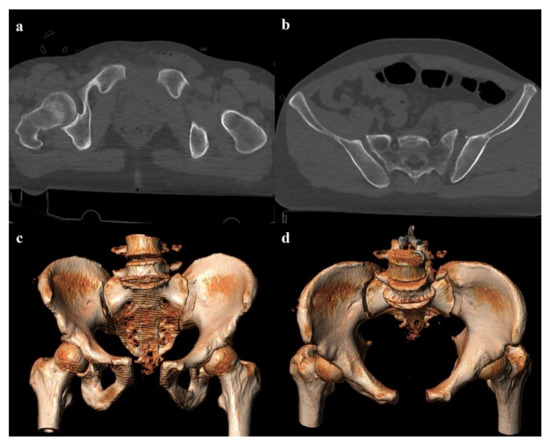

Review

Imaging Review of Pelvic Ring Fractures and Its Complications in High-Energy Trauma

by Edoardo Leone, Andrea Garipoli, Umberto Ripani, Riccardo Maria Lanzetti, Marco Spoliti, Domenico Creta, Carolina Giannace, Antonio Galluzzo, Margherita Trinci and Michele Galluzzo

Pelvic ring fractures are common in high-energy blunt trauma, especially in traffic accidents. These types of injuries have a high rate of morbidity and mortality, due to the common instability of the fractures, and the associated intrapelvic vascular and visceral complications. Computed tomography [...] Read more.

Pelvic ring fractures are common in high-energy blunt trauma, especially in traffic accidents. These types of injuries have a high rate of morbidity and mortality, due to the common instability of the fractures, and the associated intrapelvic vascular and visceral complications. Computed tomography (CT) is the gold standard technique in the evaluation of pelvic trauma because it can quickly and accurately identify pelvic ring fractures, intrapelvic active bleeding, and lesions of other body systems. To properly guide the multidisciplinary management of the polytrauma patient, a classification criterion is mandatory. In this review, we decided to focus on the Young and Burgess classification, because it combines the mechanism and the stability of the fractures, helping to accurately identify injuries and related complications. Full article